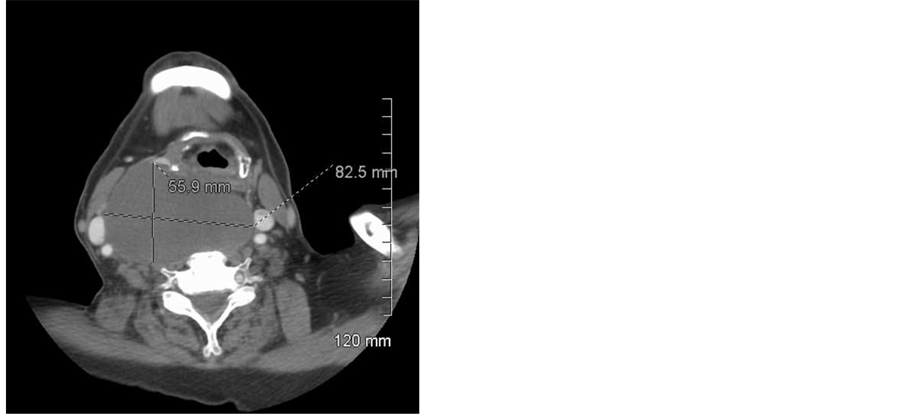

CT imaging of the neck with contrast demonstrated a complex cystic mass 8.2 × 5.6 × 10.5 cm with a 0.7 × 0.5 cm nodular and solid focus along the right lateral cyst border. The mass extended from the retropharyngeal space with mass effect on the hypopharynx, esophagus, trachea and right carotid space structures and extended into the superior mediastinum. No significant cervical lymphadenopathy was present. See Figure 1 and Figure 2.

Figure 1. Computed tomography (CT) scan with contrast of neck. This axial slice demonstrates the patient’s cystic neck mass and laryngeal deviation to the left.